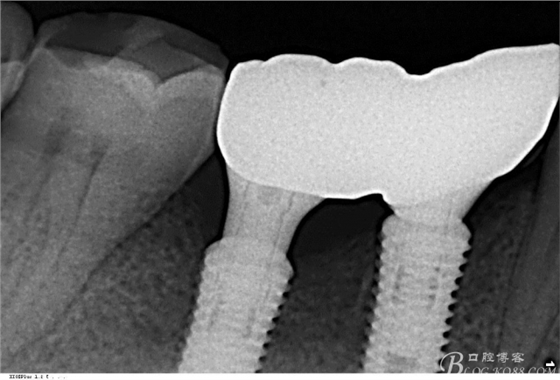

口外粘接后,口內(nèi)螺絲固位

檢查邊緣封閉及靜態(tài)密合

牙齦封閉良好,咬合,近中觸點穩(wěn)定

樹脂封閉螺絲孔